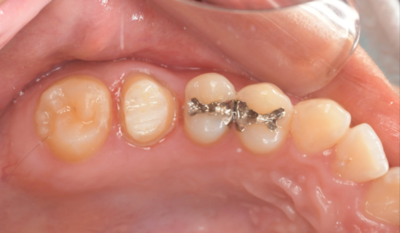

移植12ヶ月後の口腔内写真

移植12ヶ月後のレントゲン

移植12ヶ月後。セラミッククラウンで歯冠を修復した。

デンタルX線写真では透過像もほぼ消失している。